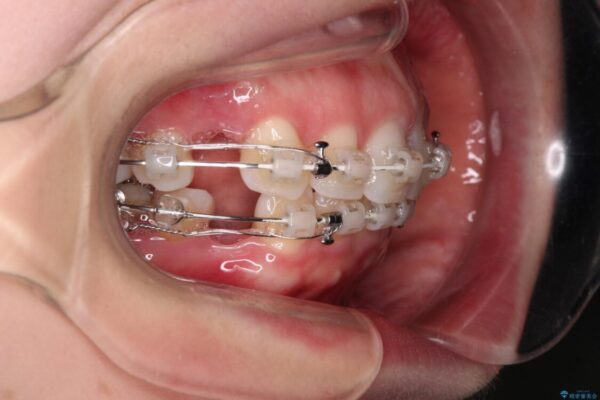

治療途中

• 【モニター】出っ歯と咬み合わせを改善 ワイヤー装置の抜歯矯正 治療途中画像

奥歯の咬み合わせ改善には1年ほどの期間と処置中の噛みにくさを強いることとなりましたが、抜歯後はスムーズに治療を完了させることができました。

歯ぎしりの際に奥歯が干渉していた咬み合わせも理想的な状態に改善できました。